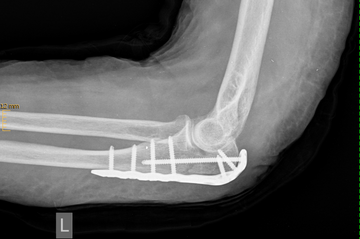

Distale Humerusfraktur

Der untere Anteil des Oberarmknochens bildet einen Anteil des Ellenbogengelenkes, auf dem sich die Unterarmknochen Elle und Speiche als Gelenkpartner bewegen. Frakturen in dieser Region müssen fast ausnahmslos operiert werden.

Häufig müssen Frakturen des Ellenbogengelenkes operiert werden, da bereits kleinere Verschiebungen der Gelenkflächen zu einem schnellen Verschleiß und einer Funktionsminderung des Gelenkes führen.

Ist dieses nicht der Fall und es liegt eine komplexe Fraktur mit verschobenen Knochenfragmenten vor, erfolgt in der Regel eine Operation. Durch den Zug der Streckmuskulatur klaffen die einzelnen Bruchstücke weit auseinander. Zur Fixierung der Fraktur und Wiederherstellung der Gelenkfunktion ist eine Verdrahtung oder Verplattung des Bruchs notwendig.